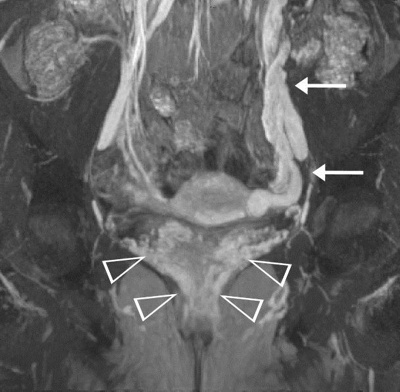

MRI des Beckens bei einer Patientin mit einem Beckenvenensyndrom und krampfartig erweiterten Venen um die Gebärmutter und Scheide (Pfeilspitzen) sowie einer massiv erweiterten linksseitigen Eierstockvene (Pfeile).